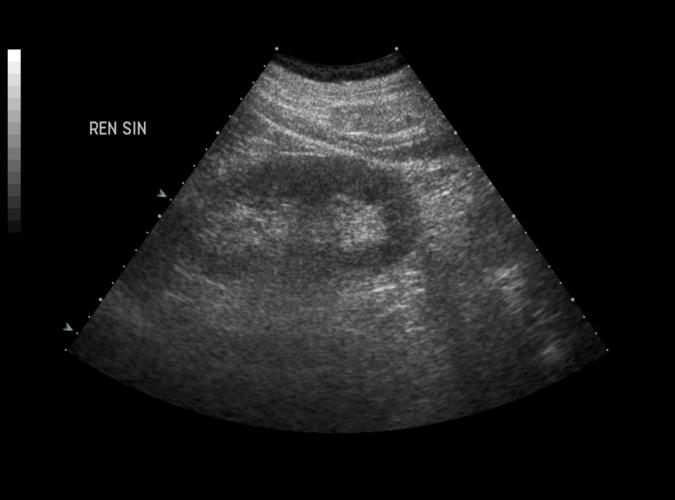

av Catherine Olsson, sonograf

Patologi.

Akut patient med vänstersidiga flanksmärtor. Long.normal vänster njure......ändå konkrement intill vänstra ostiet.(se nästa bild 9v)